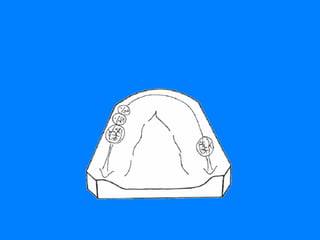

QUE SE ENTIENDE POR EFECTO DE ARCO CRUZADO ES EL EFECTO QUE SE CONSIGUE PARA LA RPR CUANDO LOS COMPONENTES DE LA MISMA UBICADOS EN UN LADO DEL  ARCO DENTAL AYUDAN A LOS COMPONENTES DEL LADO OPUESTO BUSCANDO UN MEJOR SOPORTE, ESTABILIDAD Y RETENCION. CUANDO LOS DOS LADOS DE UNA RPR SE UNEN A TRAVES DE LA LINEA MEDIA POR UN CONECTOR RIGIDO,  TODOS LOS DIENTES PILARES INVOLUCRADOS EN SU DISEÑO RECIBEN EL EFECTO DE ARCO CRUZADO. AL ENCONTRAR EN EL ARCO DENTAL DOS DIFERENTES SUPERFICIES QUE PUEDEN COLABORAR CON LAS FUNCIONES DE SOPORTE, ESTABILIDAD Y RETENCION  DE LA R.P.R. SE DEBE HABLAR DE  ARCO CRUZADO DENTAL Y MUCOSO  PARA ACLARAR A QUE FUNCION SE ESTA HACIENDO REFERENCIA

EFECTO DE ARCO CRUZADO DENTAL UNILATERAL LIMITACION 44 RESTAURACION  DENTO MUCO- SOPORTADA Hace referencia a las tres funciones, ya que los dientes pilares pueden colaborar positivamente en cada una de ellas

EFECTO DE ARCO  CRUZADO MUCOSO ESTE SE LIMITA UNICAMENTE A LA POSIBILIDAD QUE PUEDEN BRINDAR EL PALADAR Y LOS REBORDES RESIDUALES ( ARCO MAXILAR )  Y  ( ARCO MANDIBULAR ) DE COLABORAR EN LAS FUNCIONES DE SOPORTE Y ESTABILIDAD, YA QUE LA FUNCION DE RETENCION EVITANDO EL DESALOJO DE LA RESTAURACION PARCIAL REMOVIBLE ES UNA FUNCION  BASICA   DE LOS DIENTES PILARES.